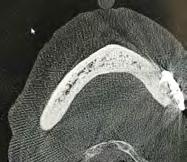

Fueron reclutados de forma retrospectiva, pacientes que presentasen atrofia ósea extrema mixta, tanto en maxilar como en mandíbula y en los que se insertasen implantes extracortos (5.5 y 6.5 mm) y de plataforma reducida de 3 mm, durante un periodo comprendido entre junio de 2020 y junio de 2021. Antes de la inserción de los implantes se utilizó una premedicación antibiótica consistente en amoxicilina 2 g vía oral una hora antes de la intervención y paracetamol 1 g vía oral (como analgésico). Posteriormente los pacientes prosiguieron con un tratamiento de amoxicilina 500-750 mg vía oral cada 8 horas (según peso) durante 5 días. Todos los pacientes fueron estudiados antes de la inserción de los implantes mediante modelos diagnósticos, exploración intraoral y realización de un TAC dental (cone-beam) analizado posteriormente mediante un software específico (BTI-Scan III).

Figura 1. Localicación, diámetro y longitud de los implantes incluidos en el estudio.

Fueron reclutados 8 pacientes en los que se insertaron 13 implantes que cumplieron con los criterios de inclusión previamente establecidos. De ellos, 3 fueron hombres y 5 mujeres con una edad media de 74.8 años (+/- 13.7). Ningún paciente era fumador y como patologías sistémicas asociadas, 2 pacientes refirieron hipertensión en tratamiento farmacológico. La posición dental más frecuentemente restaurada fue para la zona de 14, 34, 35 y 45 con un 15.4% para cada una de ellas. El resto de posiciones: 15, 24, 25, 44 y 46 tuvieron una frecuencia de 7.7%. La longitud de los implantes estudiados fue de 6.5 mm en el 69.2% de los casos y de 5.5 en el 30.8% restante. El diámetro de los implantes osciló entre 2.5 mm (23.1%), 3 mm (30.8%) y 3.3 mm (46.2%), presentando todos ellos una plataforma de

3 mm. La distribución del diámetro, longitud y posiciones de los implantes estudiados se muestran en la Figura 1